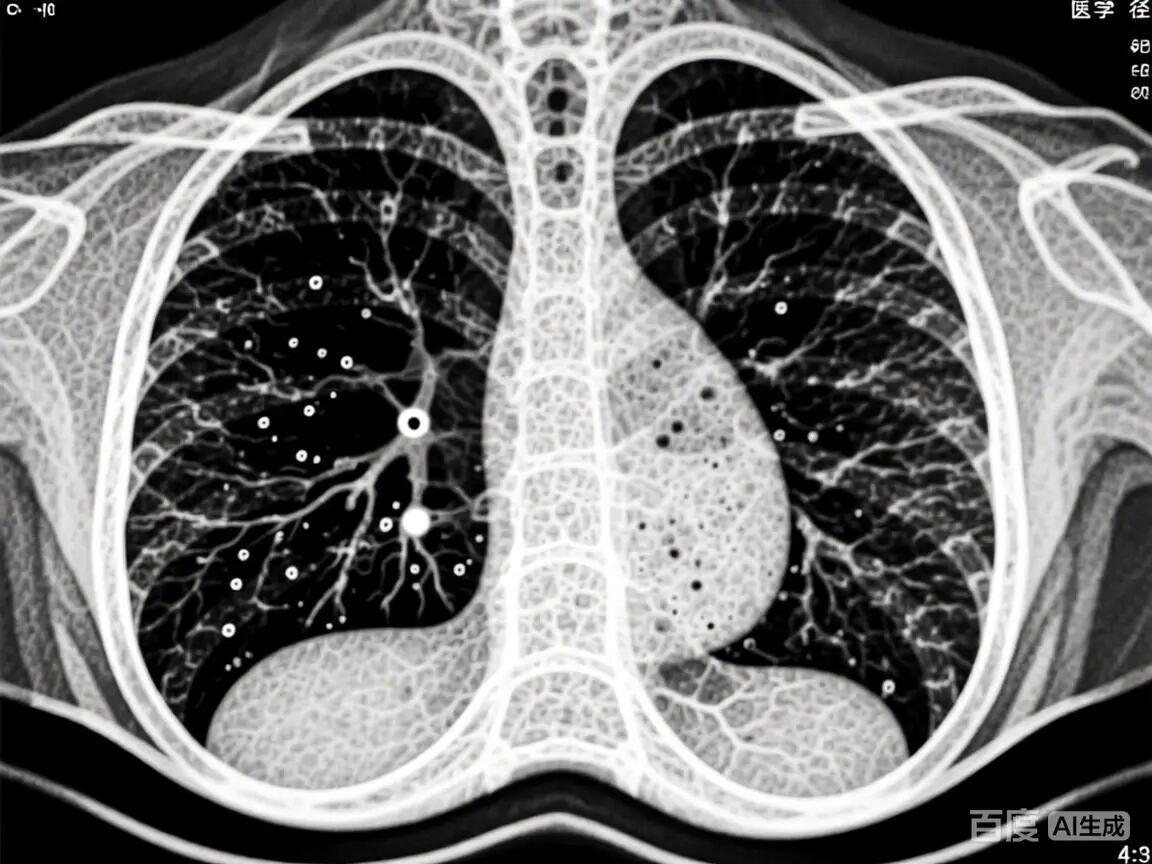

● 双源CT解决方案:低剂量螺旋CT(LDCT)是目前公认有效的肺癌筛查工具 。洛阳白马医院的双源CT能以更低的辐射剂量完成高质量的肺部扫描,清晰显示5毫米以下的微小结节,为早期诊断提供可靠依据。对于致命的肺栓塞,其“闪电般”的扫描速度能够迅速完成肺动脉血管成像(CTPA),精准捕捉血管内的血栓。